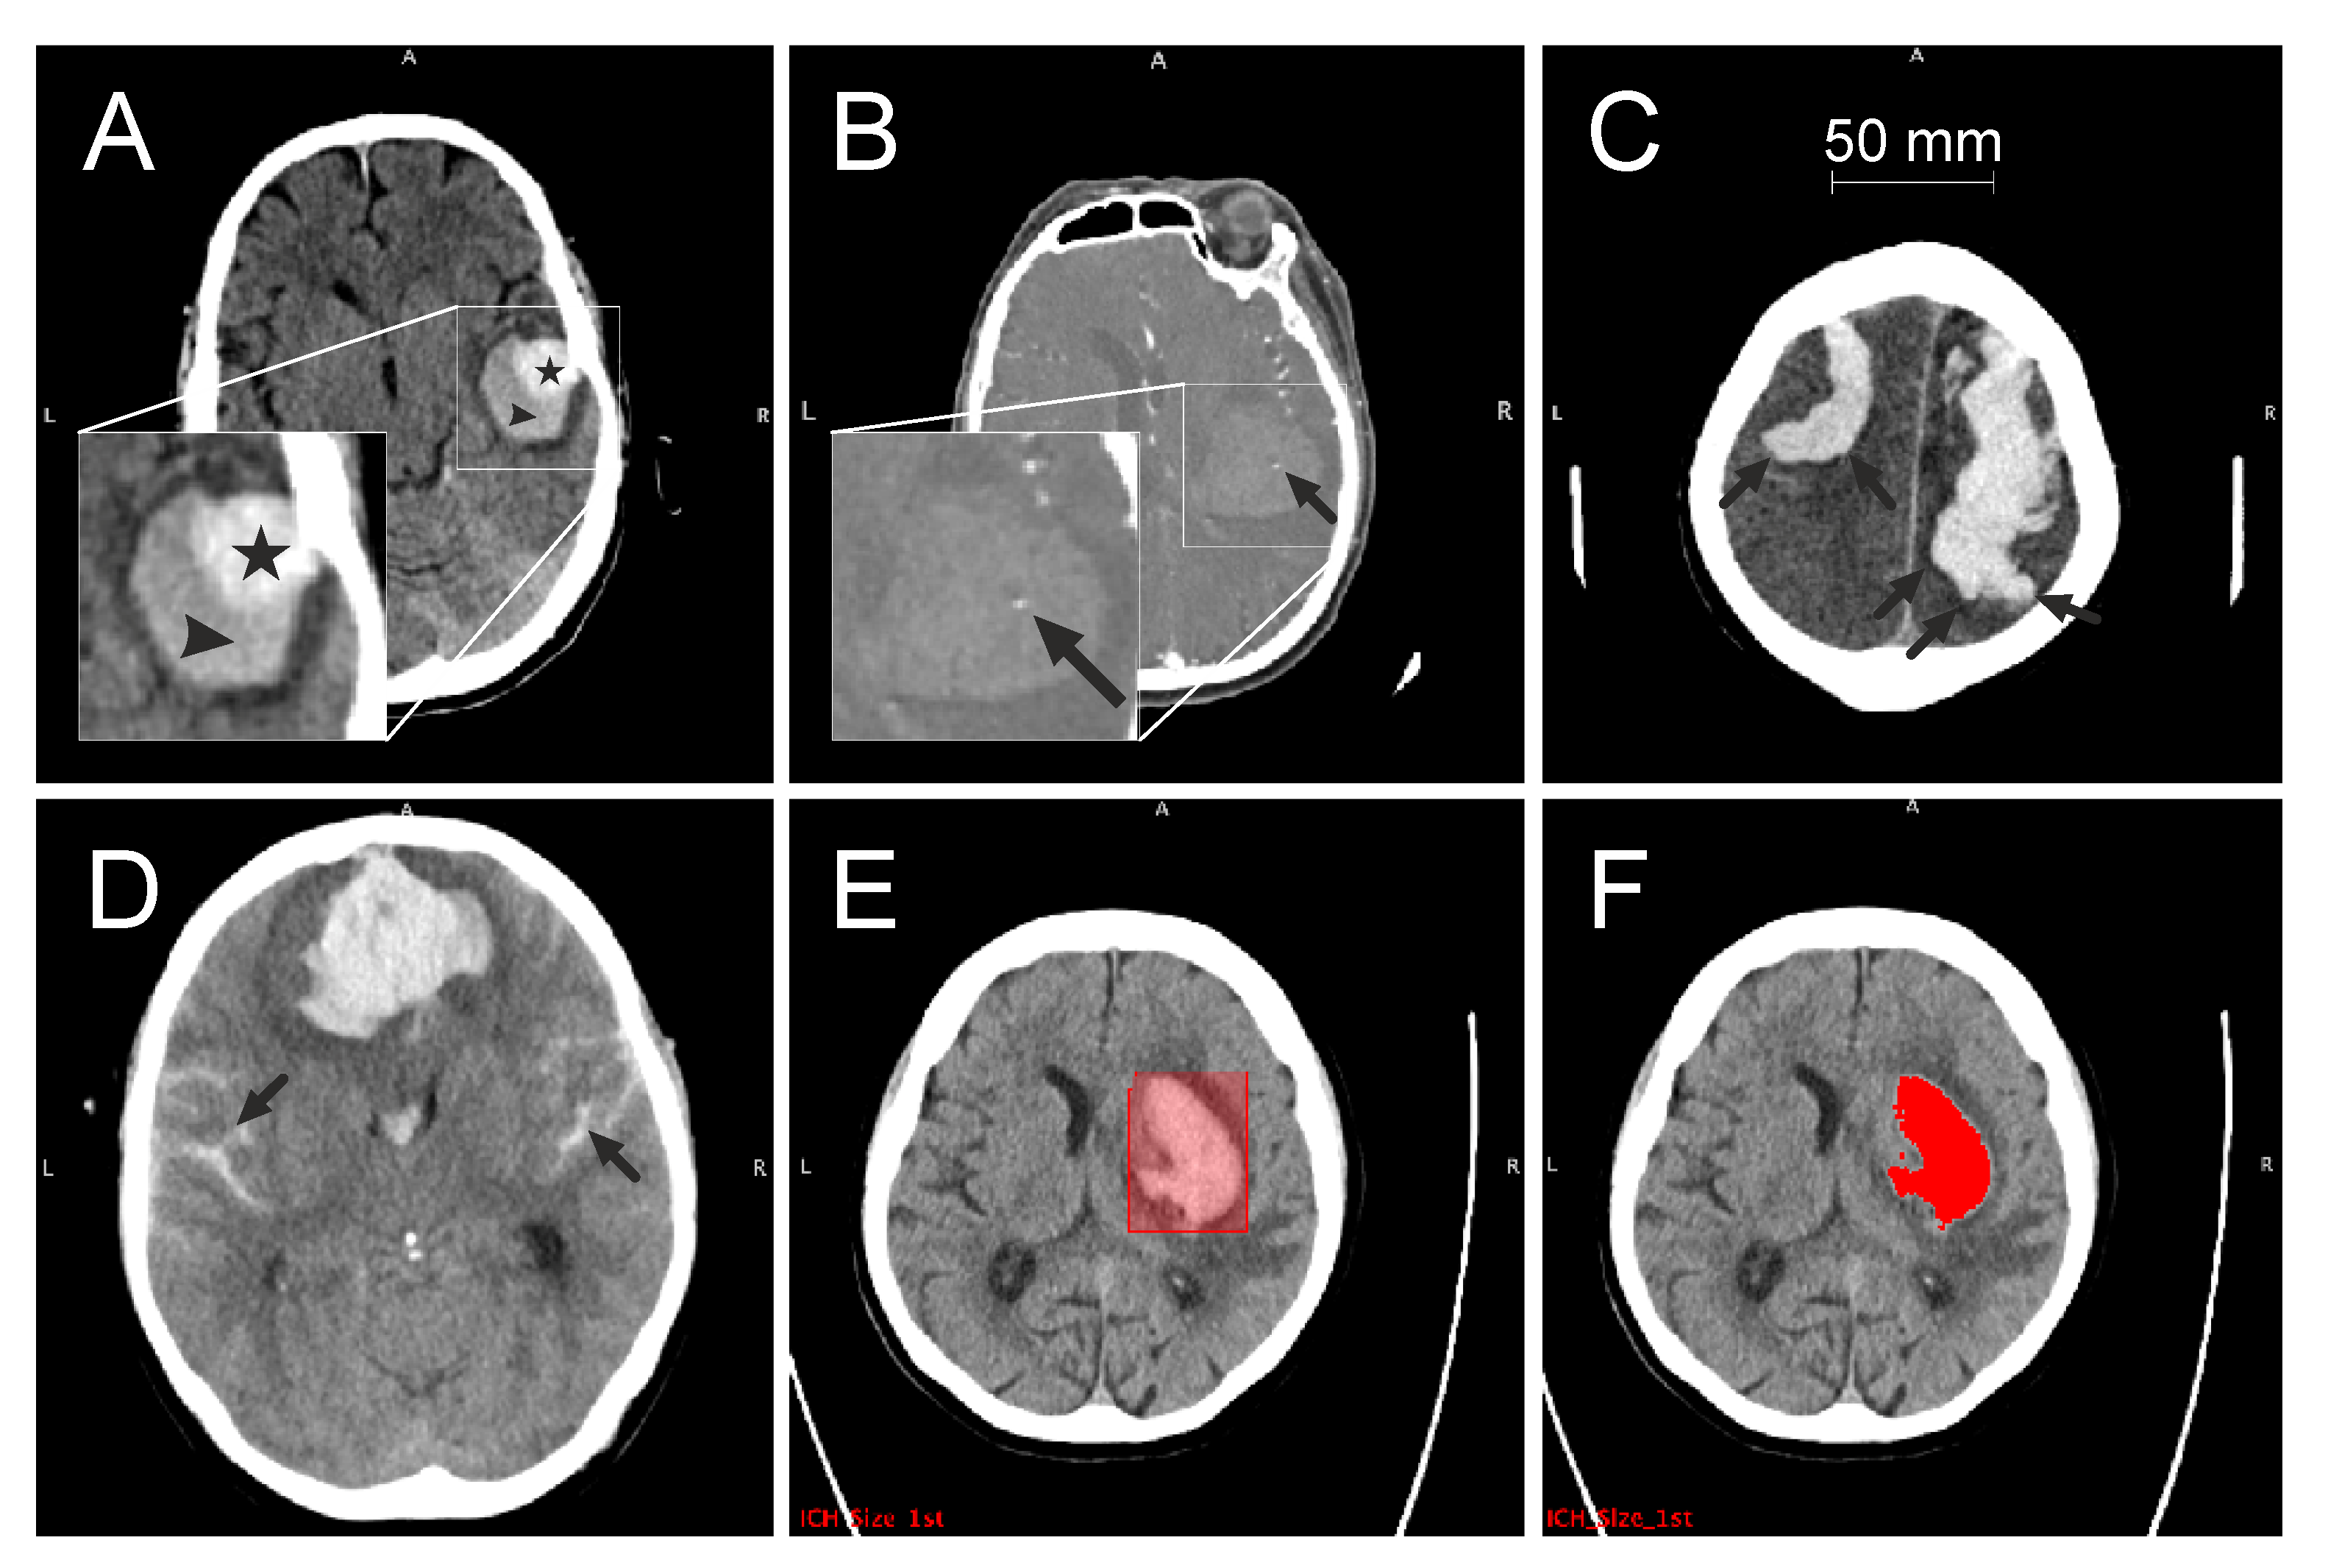

The blend sign was defined as a blend of a relatively hyperattenuated region with an adjacent hypoattenuated area within the ICH, with a well-defined margin and a minimum density difference of at least 18 Hounsfield units (HU) between these two regions [4] (Figure 2A). The spot sign was defined as at least one focus of contrast pooling within the ICH, with a minimum density of 120 HU (Figure 2B). FLP were considered as elongated extensions arising from the ICH with a shape that is longer than it is wide, regardless of whether it reaches the cortex or not [7] (Figure 2C). SAH appears as a high-attenuating, blood-filled subarachnoid space (Figure 2D).

Figure 2.

CT signs and workflow. Axial images (A–D) show different CT markers: blend sign (A) with two different areas of attenuation (triangle, star), spot sign (B) with the focus of contrast pooling (arrow), finger-like projections (C) with extensions longer than wide (arrows) and (D) subarachnoid haemorrhage (arrows). Volume quantification with the cuboid bounding region of interest (E) and derived ICH volume (F) after thresholding. CT, computed tomography; ICH, intracerebral haemorrhage.

The attenuation of ICH is usually higher, around 56 HU, whereas the density of the surrounding tissue is lower (grey matter: 37–41 HU; white matter: 30–34 HU) [1]. Density differences were used to manually draw a bounding box containing each ICH as a region of interest (ROI) (Figure 2E). For voxels contained in this cuboid ROI, an intensity threshold was calculated using Otsu’s method to separate the hyperintense ICH volume from the normo- and hypointense surrounding tissue. After a visual inspection of segmentation results (JNK), minor threshold readjustments were carried out, when necessary, to ensure consistency. The sizes of the segmented ICH were subsequently extracted (Figure 2F).